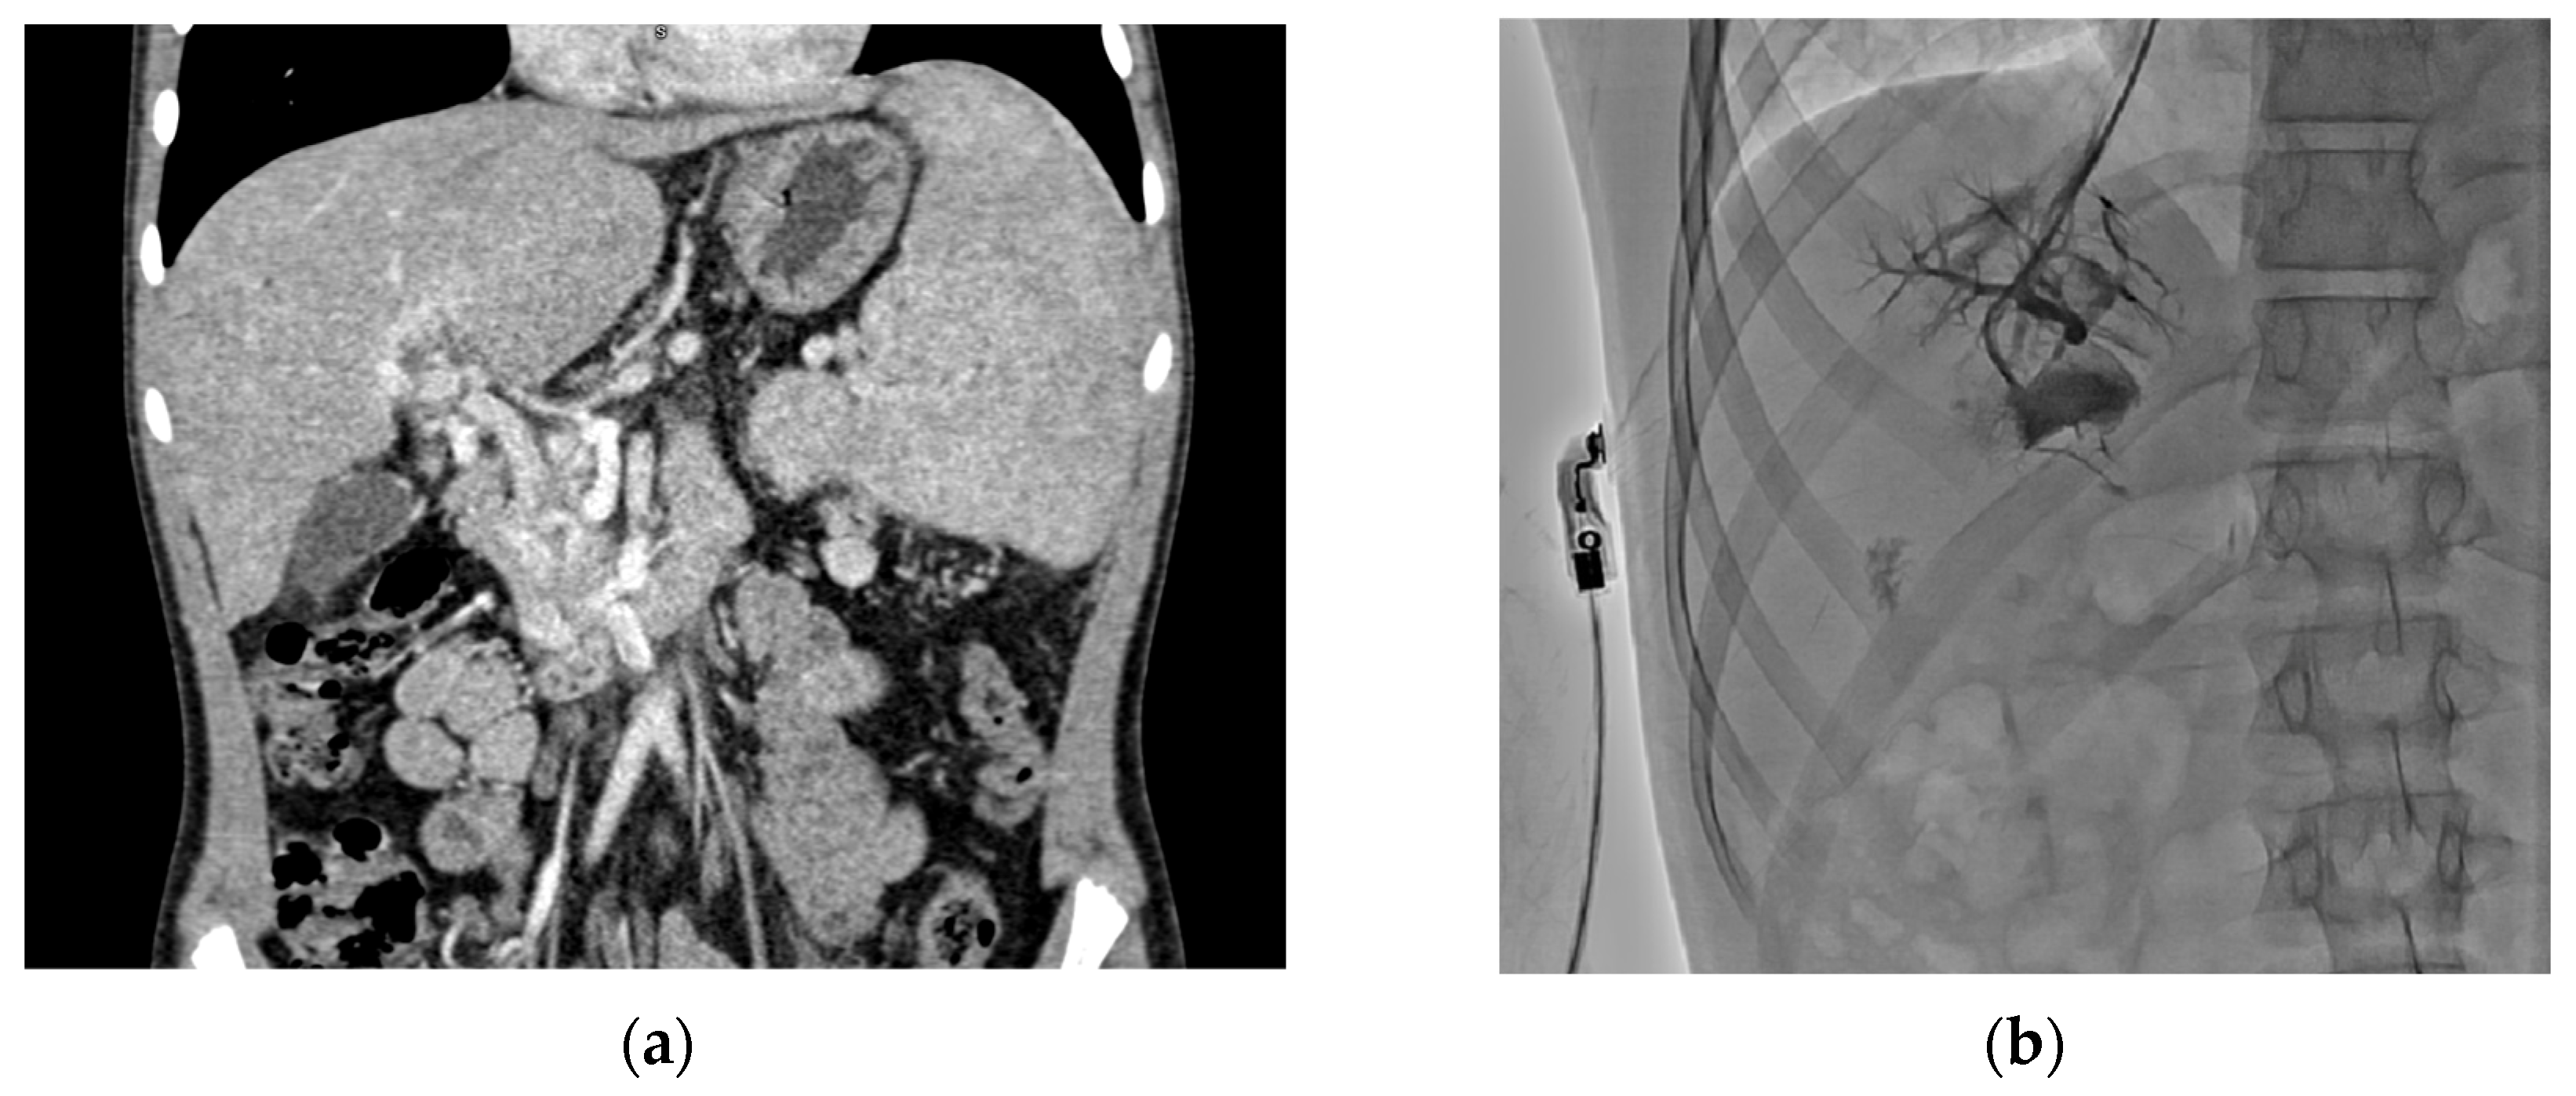

Preoperative imaging is crucial for planning surgery, as it provides anatomical information on vessel patency (e.g., superior mesenteric vein and left portal vein). CTA and MRA are effective non-invasive modalities to evaluate vessels in children. Additionally, hepatic vein portography can directly assess the Rex recess patency, though it is invasive and requires general anesthesia [28,29,30]. Notably, interpreting these imaging studies can be challenging, and failure to visualize a patent Rex vein does not necessarily exclude its presence [31]. In our study, all patients underwent CTA before surgery, and four patients also had portography performed (Figure 2).

Figure 2. Preoperative imaging: CTA image (a) visualizing cavernous transformation of the portal vein with collateral vessels and retrograde portography (b) obtained via jugular vein catheterization and visualizing patent intrahepatic portal veins.